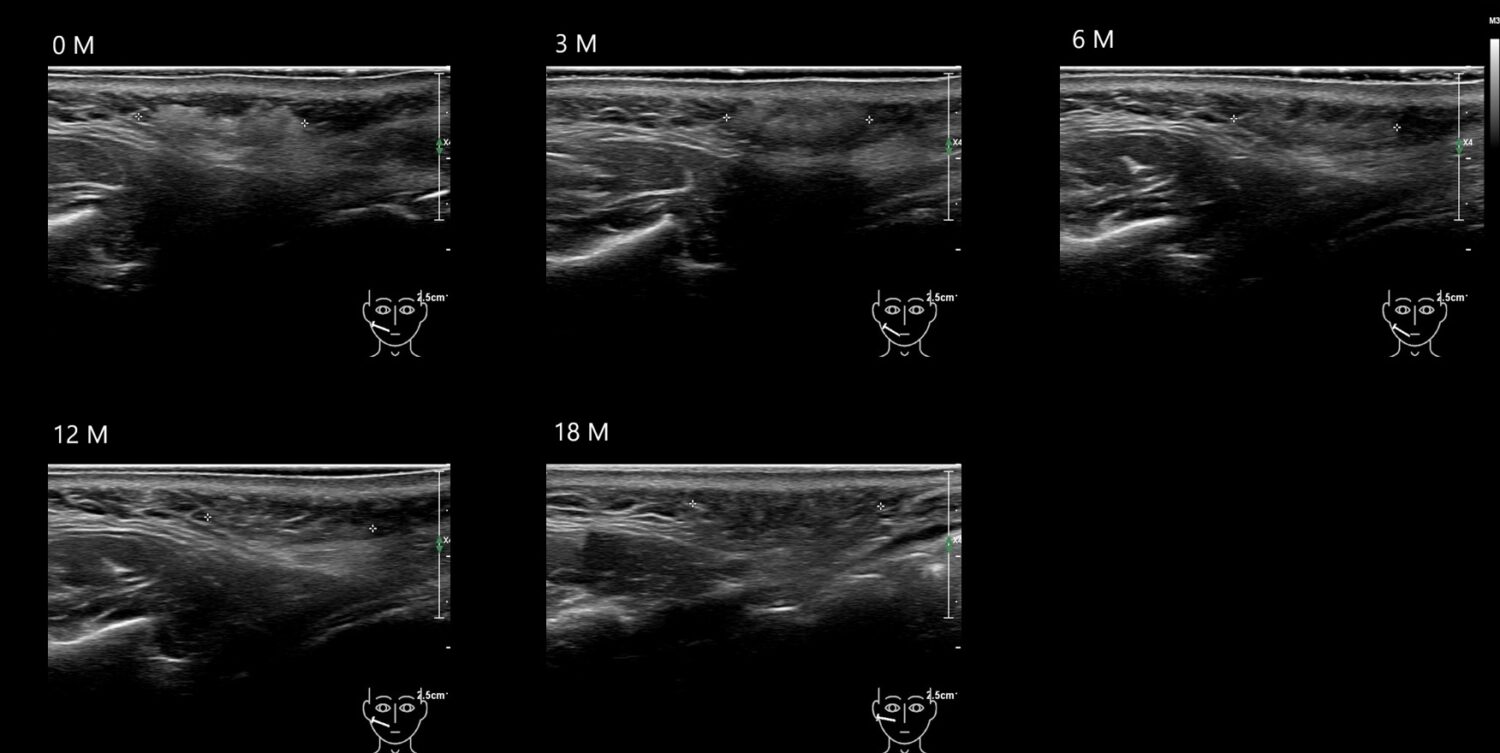

O CAHA 21 E

O CAHA11 E

O CAHA12 E

O CAHA13 E

O CAHA16 E

O CAHA20 E

o caha4 E

O CAHA5 E

o caha6 E

O CAHA7 E